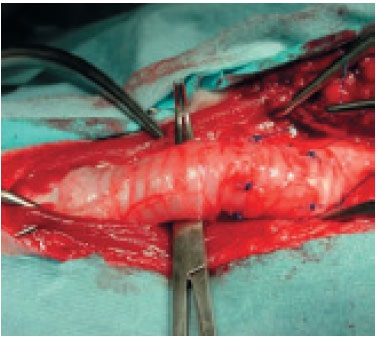

Alkalmazási technikáinak redők dorsalis tracheális membránjával betegek egy kis fokú összeomlása a légcső, amikor porcos gyűrűk megtartják alakjukat és dorsalis membrán feleslegben (1. és 2. fokozat). Bemetszést ejtenek mentén középvonalon, felfedve a nyaki légcső, majd folytatja sternotomiaból metszést bevonása esetén mellkasi légcsövet elválasztjuk. Széles gyengült tracheális membrán összevarrtuk csomózott öltések (menet - monofil nem felszívódó). Ez megakadályozza behajlást eredményez a membránon keresztül a lumen a légcső és a légúti elzáródás. Súlyos trachea porcgyűrű trachea összeomlása és lelapul dorsoventrally alkotják fele a kerülete a légcső. Ezzel kapcsolatban a technika alkalmazása során a redők dorsalis membrán nem ajánlott, mert okozhat súlyos szűkülete a lumen. Amikor a 3.-4. fok az összeomlás, amikor a szélessége a dorzális a membrán felületével felével egyenlő a kerülete a légcső, körülbelül 25% -a a kerülete a meglévő berendezések során elvész a gyűrődések kialakulása. Potenciális keresztmetszeti területe a légcső csökken mintegy 44% (A. Wendell Nelson betegségei a légcső és bronch) (ábra8).

A külső rögzítőszerkezet légcsőgyűrűket alkalmazásával elválasztottuk polipropilén. Ezek készülhetnek fecskendőhengeréhez vagy lehet az ipari termelés. Műanyag gyűrű körülveszi a légcső részlegesen lefedő azt 2/3, az szükséges, hogy a rugalmasság és a lehetőségeket, hogy mozgassa a légcső során lélegzik. Fontos, hogy a beültetés a gyűrűk nem volt zavaró a vérellátása és beidegzése a légcső. Használata gyűrűk különböző átmérőjű, a belső átmérője van kiválasztva átmérőjétől függően a légcső. Külső stabilizáció, nézetünk szerint kell használni nyaki összeomlás és közelebbi mellkasi összeomlása miatt beállítás a külső része az implantátum a mellkas rendkívül nehéz megvalósítani, nem komolyan megzavarják a funkció a vérellátása és beidegzése (9. ábra).

Operatív keresztül elérhető egy középvonali hasi bemetszést a garat a mellkasi belépő. Támasztógyürü egymás felett helyezkednek dorsoventral oldalán a légcső. A gyűrűk kapcsolódnak a légcső útján ízületek 5, amelyek egymáson vannak, mindegyik gyűrűn. Erre a célra az egyes támasztógyűrű előzőleg kifúrt öt nyílások: egy nyílás mindkét végén gyűrű, egy mindkét oldalán oldalirányban és dorsalis membrán. Varratokat alkalmaznak monofil szállal nem felszívódó (5-0), a további szövet varrt rétegekben (10. ábra).